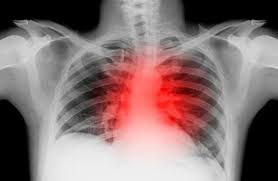

3. 폐·호흡기 문제

- 흉막염, 폐렴: 숨이나 기침할 때 날카롭고 찌르는 통증, 발열·기침 동반 :contentReference[oaicite:4]{index=4}.

- 기도 폐색(폐색전증 등): 갑작스럽고 큰 통증 + 호흡 곤란은 즉시 응급 대응 필요 :contentReference[oaicite:5]{index=5}.

- 기흉: 한쪽 가슴 급성 통증 + 숨참이 나타나면 병원 긴급 방문 :contentReference[oaicite:6]{index=6}.